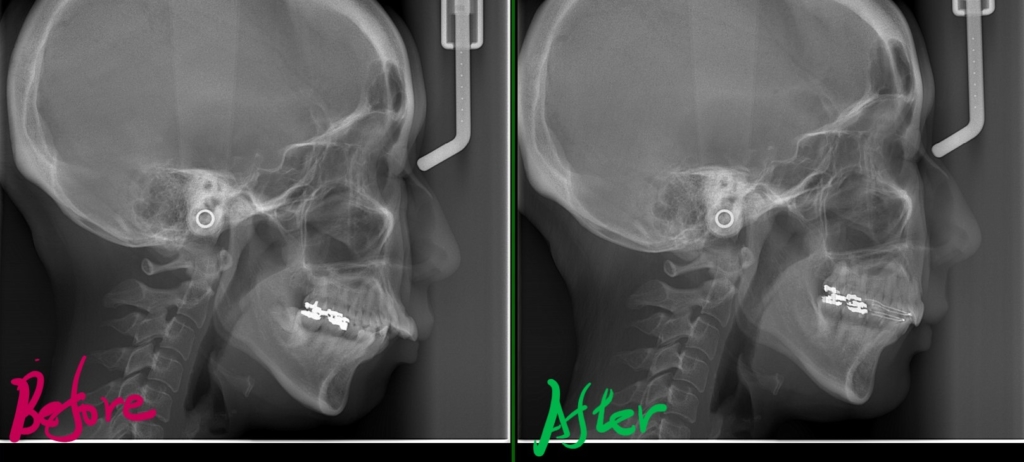

左側が矯正治療前、右側が矯正治療後

矯正後の状態をレントゲン写真で確認すると、

では、矯正治療前後の「レントゲン写真」や「歯並び」「横顔と口元の写真」などを比較してみましょう。

まずはレントゲン写真の比較です。